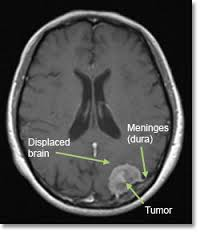

Beynimiz jelatin kıvamında bir dokudur ve beyin omurilik sıvısının içinde adeta yüzmektedir. Bu sıvı ayrıca beynin derininde yer alan ventrikül adı verilen boşlukları doldurmaktadır. Böylece beyin sarsıntıdan etkilenmez ve beyin omurilik sıvısı içinde batmaz bir şekilde yüzmektedir.

Beyin omurilik sıvısı ventriküller boyunca birbiriyle bağlantı yapan kanallar sayesinde devirdaim yapmaktadır.

Beyin omurilik sıvısının üretim, akım ve emilim süreci arasındaki varolan hassas denge, sıvının kafa içerisinde normal basınç altında devirdaim yapabilmesi açısından çok önemlidir. İşte hidrosefali denilen klinik tablo bu hassas dengenin bozulması durumunda ortaya çıkar. Örneğin ventriküller arasında geçişi sağlayan kanalların daralması veya sıvının emilmesinde bir hasar olması gibi sıvının devirdaimi sürecinde herhangi bir basamakta aksama olması hidrosefali oluşumuna neden olmaktadır.